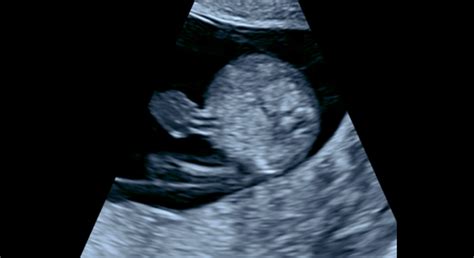

V šiestom týždni embryo dosahuje veľkosť približne 8 milimetrov a váži okolo 1 gramu. Začínajú sa formovať základy končatín, ktoré pripomínajú malé pádielka, a v oblasti hlavy sa vyvíjajú základy očí, nosa, úst a uší. V 6. týždni hladina progesterónu prudko stúpa a ozývajú sa tehotenské nevoľnosti. Snažte sa ich zvládať tým, že budete jesť menšie porcie. Plod v 6. týždni meria asi 8 milimetrov a váži približne 1 gram. Srdiečko, kde sa tvoria komory, začína biť asi 100-130-krát za minútu. V 6. týždni tehotenstva vás možno čaká prvé ultrazvukové vyšetrenie. Prvýkrát tak budete môcť svoje dieťatko uvidieť, aj keď do podoby bábätka bude mať ešte veľmi ďaleko. Ak vás lekár na ultrazvukové vyšetrenie zatiaľ neodporučí, nezúfajte - dočkáte sa v 7. týždni.

V siedmom a ôsmom týždni dochádza k doslova divom vo vývoji. Vytvárajú sa základy pre dvadsať mliečnych zubov, formuje sa dýchacia trubica a orgány ako pečeň, pankreas či slepé črevo sa ďalej vyvíjajú. Na končatinách sa začínajú oddeľovať prsty a embryo sa už začína jemne hýbať, hoci tieto pohyby matka zatiaľ nepociťuje. V 7. týždni vaša maternica sa zväčšila približne do veľkosti citróna. Pravdepodobne pretrváva pocit únavy a môže sa objavovať vracanie. Pozornosť venujte starostlivosti o svoj chrup, ktorý môže počas tehotenstva trpieť. Drobné črty bábätka ako sú oči, nos, ústa a uši začínajú byť zreteľnejšie. Nervové bunky sa ďalej množia a vyvíjajú - formuje sa nervový systém. V tomto týždni sa už určite môžete tešiť na prvý ultrazvuk. Ten prebehne vaginálne - lekár skontroluje zväčšenie maternice a prekrvenie krčka maternice. Pri prehliadke vám môže byť zmeraný tlak, skontrolovaná hmotnosť a vyšetrený moč.

V 8. týždni stále môžu pretrvávať pocity na vracanie a nevoľnosť. Medzi najčastejšie tipy, ako si s nimi poradiť, patrí mať neustále niečo v žalúdku - snažte sa jesť menšie porcie častejšie počas dňa. Medzi ďalšie príznaky patria aj bolesti hlavy a zvýšená citlivosť na pachy. V priebehu tohto obdobia pravdepodobne zaznamenáte aj zvýšenú produkciu bieleho krémového výtoku z pošvy. Ten vzniká v dôsledku vyššej hladiny estrogénu a nie je dôvodom na obavy. V malých končatinách bábätka sa vyvíjajú nervy, kosti a svaly. Na končatinách, ktoré dosiaľ vyzerali ako pádielka, sa oddeľujú prsty. Bábätko sa začína hýbať - prvé pohyby začínajú približne v 7. až 8. týždni a sú viditeľné na ultrazvuku. Pohyby bábätka však pocítite až niekedy medzi 16. a 22. týždňom.

Dvanásty týždeň, na konci prvého trimestra, je obdobím intenzívneho rastu. V 12. týždni vaše telo sa naplno pripravuje na celé tehotenstvo. To sa prejavuje nielen náhlymi zmenami nálad, ale aj zväčšením prsníkov a tmavnutím bradaviek. U niektorých budúcich mamičiek sa tiež objavujú pigmentové škvrny v oblasti tváre a krku. Vytvoriť sa môže aj pigmentová čiara označovaná niekedy ako tzv. linea negra, ktorá sa tiahne od pupka smerom nadol. Bábätko na konci prvého trimestra naozaj rastie „ako z vody“. V tomto období by ste už mali mať za sebou jedno ultrazvukové vyšetrenie, počas ktorého sa určil počet plodov, ich vitalita a rozmery. Prvé veľké ultrazvukové vyšetrenie väčšinou prebieha až v 13. týždni. V tomto týždni vás čaká prvé veľké ultrazvukové vyšetrenie. Jeho dĺžka sa odvíja od toho, akú pozíciu vaše bábätko zaujme. V tomto období budete tiež absolvovať krvné testy, ktoré spolu s výsledkami z ultrazvuku slúžia na vylúčenie genetických vád ako je napr. Downov syndróm. Na tomto ultrazvuku sa lekár zameria najmä na genetické vady.

Do 13. týždňa: prvý ultrazvuk (okolo 6.-8. týždňa), prvý prenatálny screening (11.-13. týždeň), krvné testy (napr. kombinovaný prenatálny skríning v 12. týždni). Okolo 6.-8. týždňa sa zvyčajne vykonáva prvé ultrazvukové vyšetrenie, ktoré potvrdí tehotenstvo, určí jeho lokalizáciu a vitalitu plodu. Medzi 11. a 13. týždňom tehotenstva sa realizuje kombinovaný screening vývojových chýb. Tento screening pozostáva z odberu krvi na stanovenie hladiny dvoch tehotenských hormónov (PAPP-A a hCG) a z ultrazvukového vyšetrenia. Cieľom je určiť riziko chromozomálnych odchýlok, najmä Downovho syndrómu. Lekári sledujú tzv. NT (nutkavú priehľadnosť šije) a prítomnosť nosovej kosti, ktoré môžu byť indikátormi chromozomálnych abnormalít.